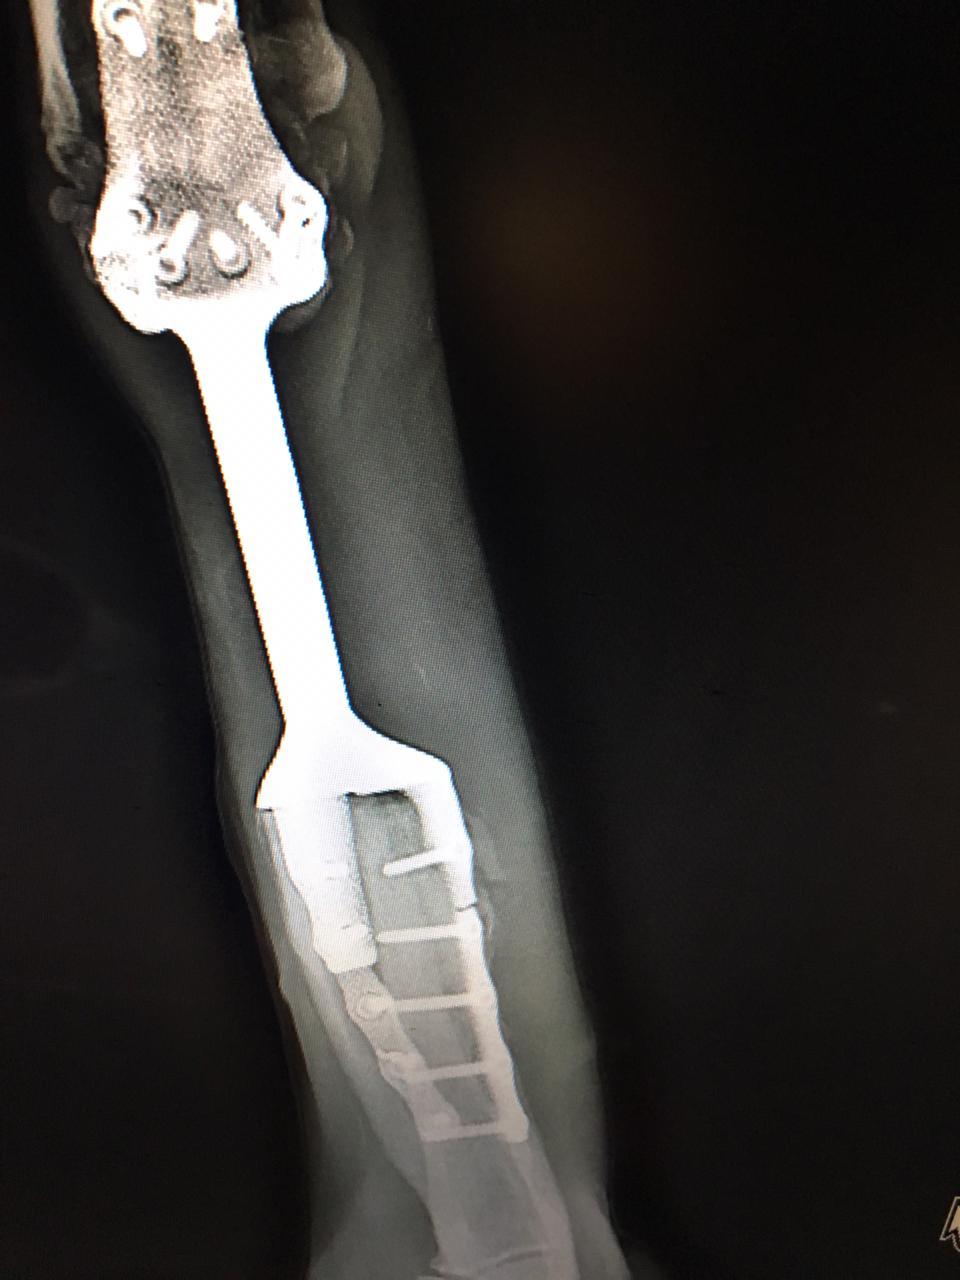

Через некоттрое время после операции, оказалось что титан треснул там, где крепился к кости. Хирург сказал, что это не страшно, т. к. это больше дополнительные крепления чем основные, но в голову лезли всякие гадости.

После 4 болта в креплении отчетливо видна трещина. Мы забеспокоились, но решили что это действительно не страшно. Собственно так и оказалось (по крайней мере пока), жопа пришла с другой стороны.